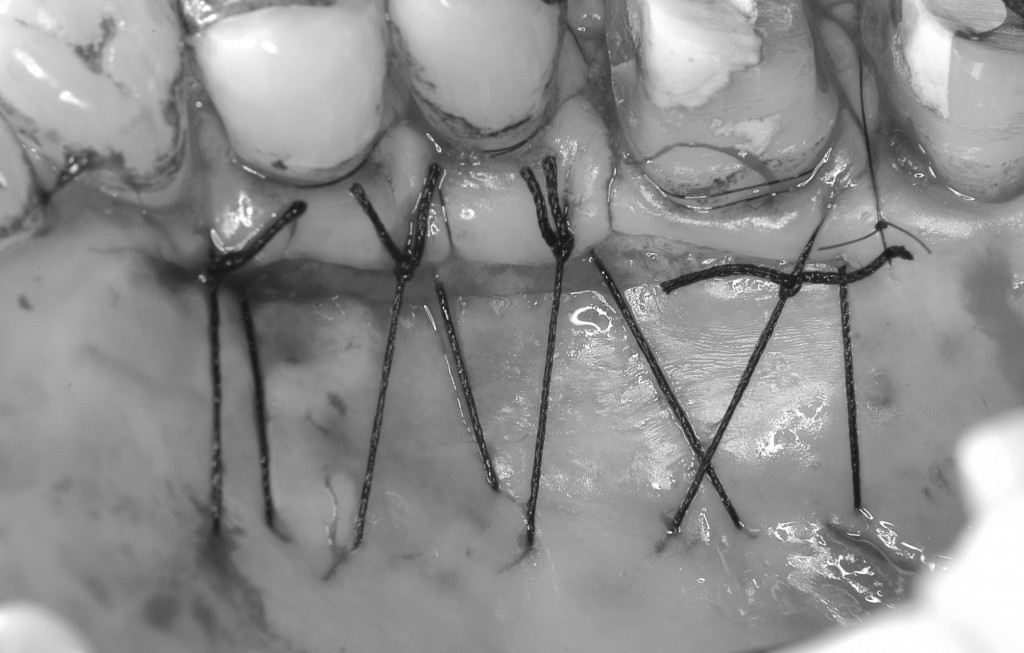

上顎の内側から結合組織(歯茎)を採取します。これを歯肉退縮部(歯茎がやせたところ)に縫い付けて,根っこを覆います。

結合組織を採ってきた部分です。採取した後に縫合してあります。ここの傷は術後,硬い食べ物などが当たらないように気をつけていただきます。術後1〜2週間で良くなってきます。

結合組織を縫合しました。